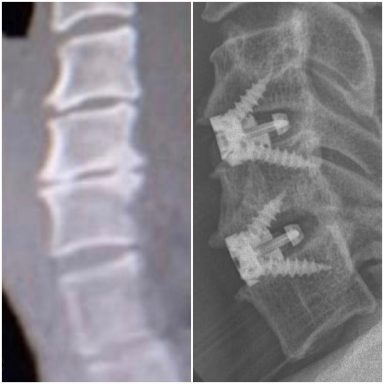

Cuando a pesar de la medicación, el deporte, y mi vida saludable, llegó un punto en el que ya no sentía alivio, decidí volver al traumatólogo para comprobar que la hernia no estaba pinzando demasiado la raíz, pero la sorpresa fue que en la RMN, se observaba la existencia bastante evidente de Romanus. Mucho más del que pueda verse en cualquier degeneración vertebral por el paso del tiempo.

En la zona cervical, grandes osteofitos en C5-C6 y C6-C7 posteriores que protuyen en el canal medular produciendo una estenosis foraminal bilateral, y anteriores que protuyen hacia el esófago, por lo que me realizan una artrodesis cervical, quitando todo el osteofito posterior.

Las vértebras L4-L5, totalmente colapsadas, y apófisis transversas impactando en la cresta iliaca, dieron el resultado final de una cojera permanente, por lo que me realizan una artrodesis lumbar con OLIF.